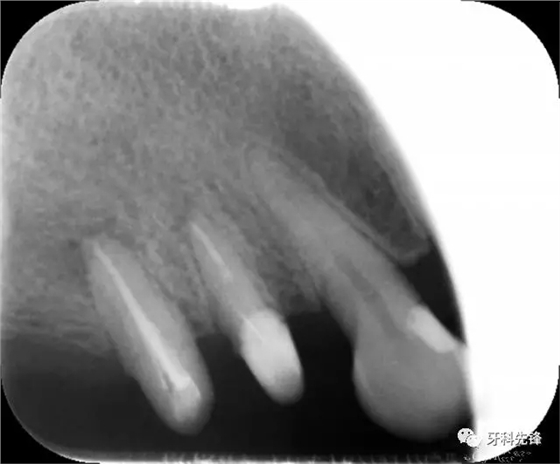

圖1術(shù)前X光片

X 示:15 根管透射,根尖有陰影

14根管阻射,恰填,無異常

46 根管阻射,恰填,根分叉骨密度降低,近中根尖陰影較大

圖1814 15 三個月后X光片(根尖陰影減小)